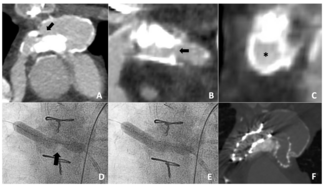

A 55-year-old man with Stanford type B aortic dissection underwent thoracic aortic and left common carotid artery mulched stent implantation. He was admitted to our hospital after surgery with low urine output, and it was suspected that the...